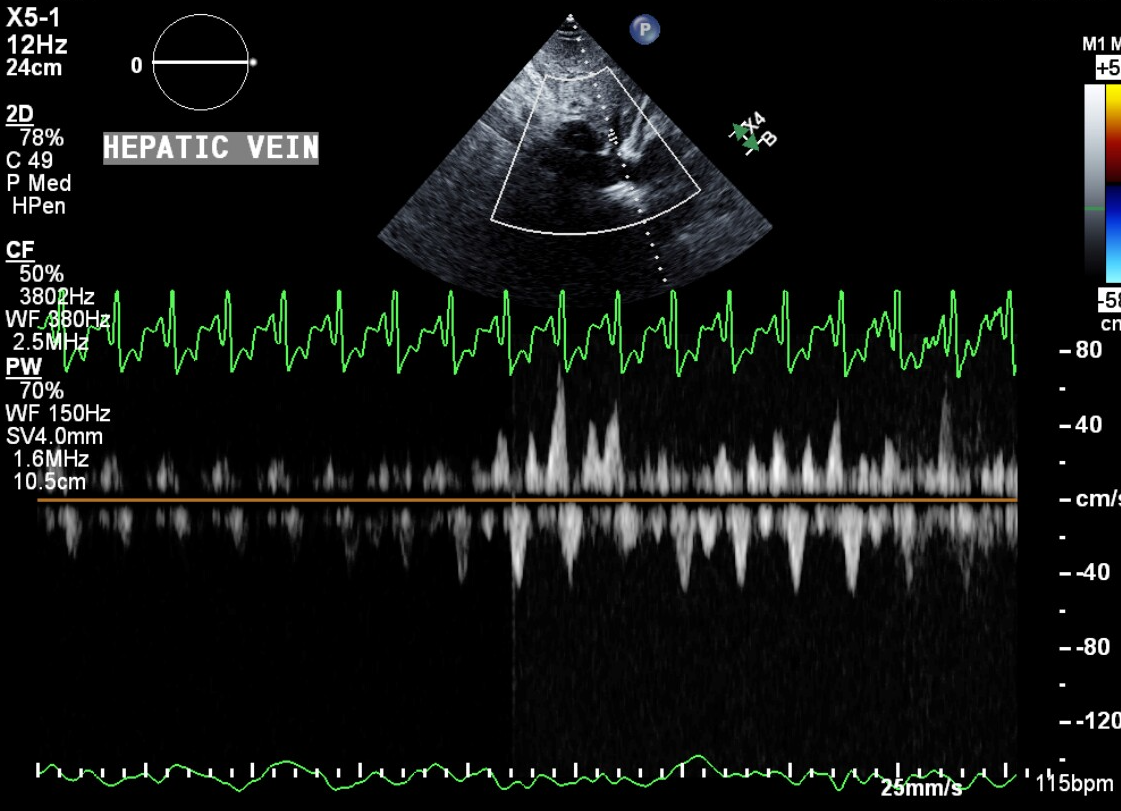

Hepatic Vein Flow Reversal Tamponade Toolbox Tamponade Hepatic Vein 40 the superior vena cava is intrathoracic and is. Any of the three hepatic veins (right, middle and. Severe venous congestion, as in cardiac tamponade, can be seen as a reversal of blood flow in the hepatic veins. Hepatic vein (hv) flow pattern closely correlates with pressure changes in the right atrium. Cardiac tamponade is a condition that causes impaired. Tamponade Hepatic Vein.

Tamponade Hepatic Vein . Cardiac tamponade is a condition that causes impaired cardiac filling due to a high pericardial pressure and increased amount of fluid within. Hepatic vein (hv) flow pattern closely correlates with pressure changes in the right atrium. Abnormal hepatic vein venous flow refers to inspiratory systolic predominance of hepatic vein forward flow,. Furthermore, diastolic flow reversal of the hepatic veins is also characteristic of cardiac tamponade. Any of the three hepatic veins (right, middle and. Severe venous congestion, as in cardiac tamponade, can be seen as a reversal of blood flow in the hepatic veins. Hepatic and portal vein doppler ultrasounds are venous hypertension. 40 the superior vena cava is intrathoracic and is.